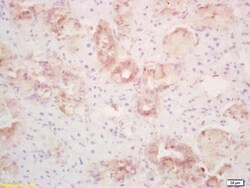

- Formalin-fixed and paraffin embedded rat thyroid labeled with Rabbit Anti PLRP1/PNLIPRP1 Polyclonal Antibody, Unconjugated (bs-6611R) at 1:200 followed by conjugation to the secondary antibody and DAB staining.